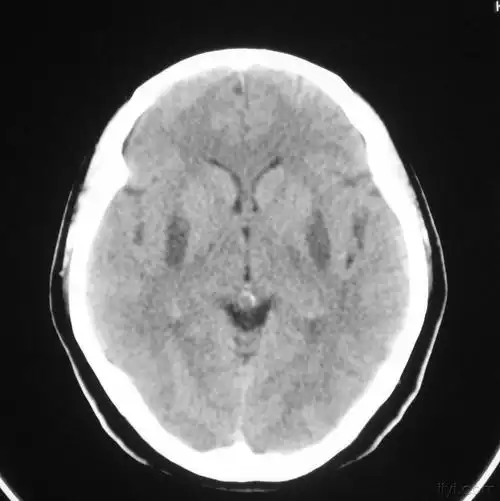

头颅ct提示:左侧基底节区脑出血.出血量大于30ml.